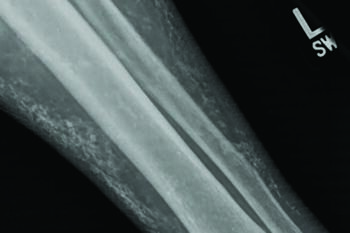

An 86-year-old male with type 2 diabetes presented to the office for evaluation and management of open ulcerations to his left anterior leg. The patient noted scraping the front of the leg on a bicycle pedal roughly one year prior with progressive enlargement of the original small wound (see first photo above). He also noted a 10- year history of purple discoloration with tight, friable skin and mild edema to the left leg only. Previous care from an outside wound healing center included serial debridement, collagenase SANTYL (Smith and Nephew), compression dressings and other modalities.

The patient returned to his primary physician who ordered labs including complete blood count (CBC), basic metabolic panel (BMP), serum rheumatoid factor (RF), erythrocyte sedimentation rate (ESR), antinuclear antibody (ANA), and Sjogren’s antibody. Testing only revealed a slightly elevated fasting blood sugar. The primary care physician then referred the patient to the primary author for evaluation. Clinical exam showed multiple granular ulcers on the left anterior leg with loose, small calcific masses (previously documented as “bone chips”) within several ulcers. Dorsalis pedis (DP) and posterior tibial (PT) pulses were palpable. The patient had varicosities, hemosiderosis and indurated skin along the anterior left leg. Protective sensation of the extremity was intact. Following physical examination, we performed two, three-mm punch biopsies; one within an open ulceration and one periwound. Pathology revealed deep dermal sclerosis with osteoma cutis and hemosiderin deposition, no evidence of malignancy.